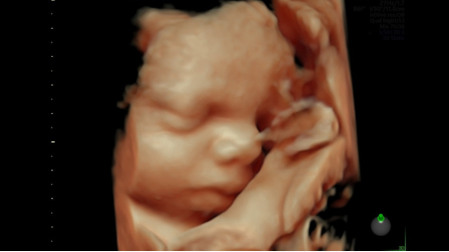

Режим Voluson HDlive позволяет добиться дополнительной глубины и четкости объемных данных

3D SonoRenderLive инновационная технология, позволяющая определять чёткие границы лица, конечностей плода, а также контуры внутренних органов в объёме без посторонних шумов